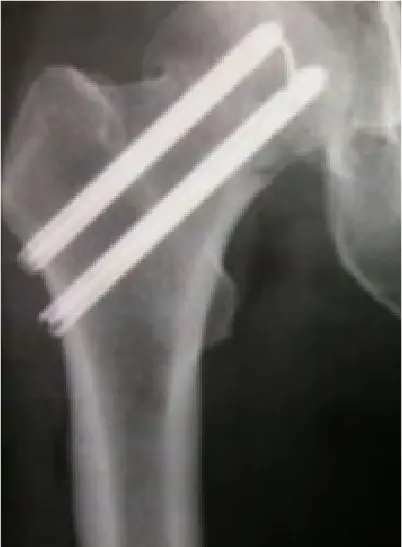

全国の病院では、大腿骨骨折の手術までに平均4〜5日かかるのが現状です。当院では原則48時間以内の手術を目標とし、万全の体制を整えています。大腿骨骨折は「治療の早さ」が回復を左右する重要な疾患だからこそ、これほど手厚く手術室を確保し、患者さんの一日も早い回復を支えます。